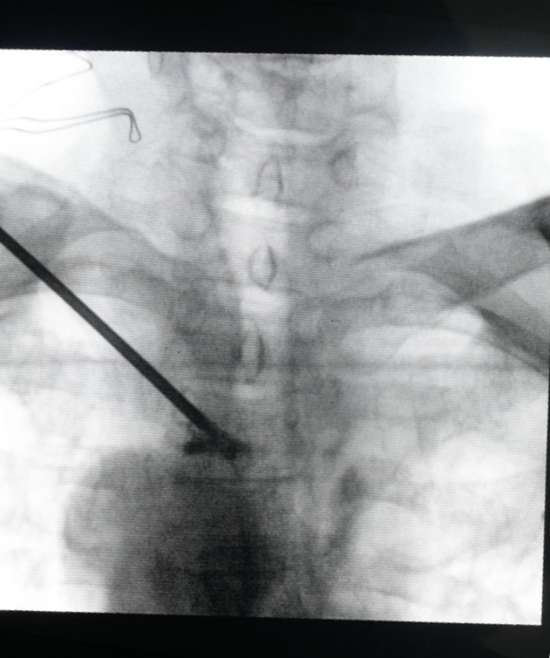

近日,禹城市人民医院骨科二病区成功为一位100岁的患者行胸3椎体压缩性骨折椎体成形术。

术前影像图片

该患者因后背部疼痛2个月入院,行胸椎CT检查显示,患者的T3椎体及其附件骨骨质破坏,食管(胸部下段)管壁增厚并纵隔,腹腔淋巴结肿大。结合放疗病房王兴主任的会诊意见,考虑老人出现的食管肿瘤合并淋巴结及骨转移并伴随T3椎体严重破坏,极容易发生骨不良事件,也就是T3椎体塌陷,老人出现高位截瘫。

本次手术的难度主要集中于:空间小(胸椎T3椎体骨折脊柱破坏平面高,手术操作空间极小);距离近(切近于升主动脉弓及脊神经、肺叶);状态差(患者已过期颐之年,又处于食道癌晚期);定位难(双侧肩胛骨与第三胸椎平齐,透视难度大)。手术的难度远远超出了一般骨科手术的范围,甚至有些困难,在医院都没有前例可循。如何翻越压在病患身上的“四座大山”,成为了医护人员深思苦索的头等大事。